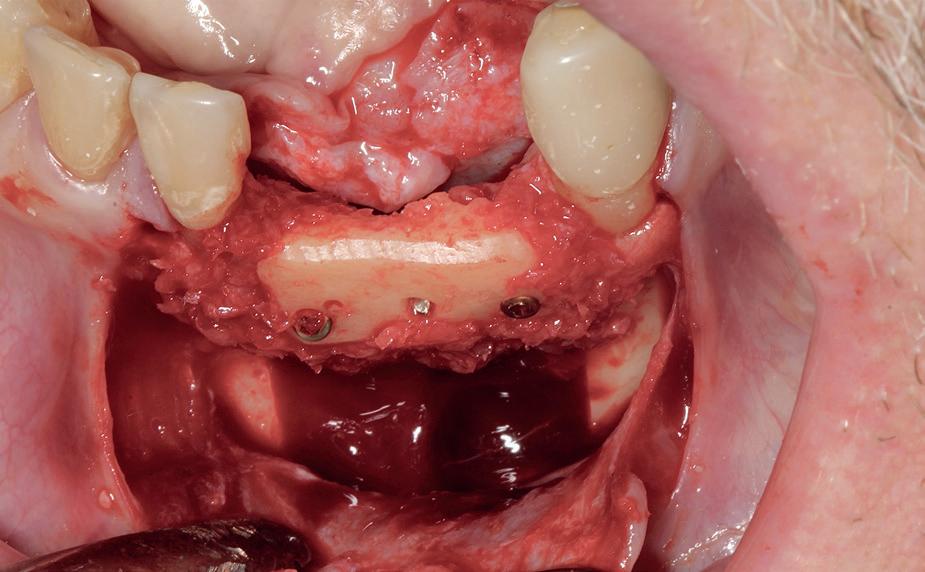

Uitvoering restauratieve fase

In het onderfront werd autoloog bot geoogst uit de kin regio ten behoeve van augmentatie (afbeelding

9. Botopbouw onderfront

9). In de bovenkaak werd bilateraal een sinuslift uitgevoerd. Aansluitend werden in beide kaakhelften implantaten geplaatst (afbeelding 10).